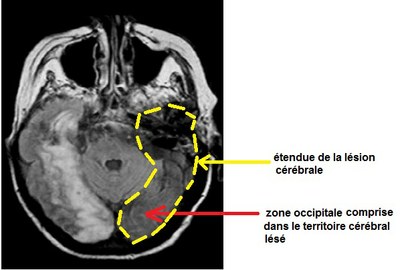

IRMpatientY

Anne Florimond

Dernière modification

27/10/2015 16:56